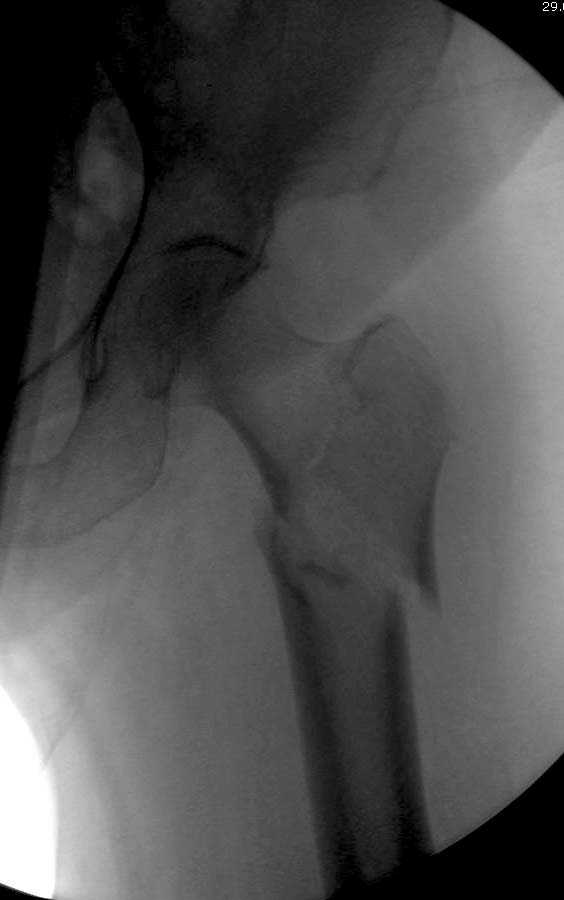

Здесь представлен случай, где в послеоперационном периоде обнаружена техническая ошибка, Gamma 3 установлен с нарушением методики. Больная в 91 лет, прооперирована через день после поступления и выписана через 48 часов.

При первом послеоперационном поликлиническом осмотре больная предъявила жалобы на боли в бедре. В серийных снимках обнаружен продольный перелом верхнего отдела бедра.

Считаем, что техническая ошибка произошла во время установки гвоздя, когда рассверливанию канала не уделили должного внимания. Канал остался узковат, и гвоздь был забит с силой. Полная нагрузка конечности приостановлена на две недели, и боли в конечности изчезли. Больная начала нагрузку и перелом срастается.-- Djoldas Kuldjanov, M.D.Associate ProfessorDepartment of Orthopedic SurgerySt. Louis University